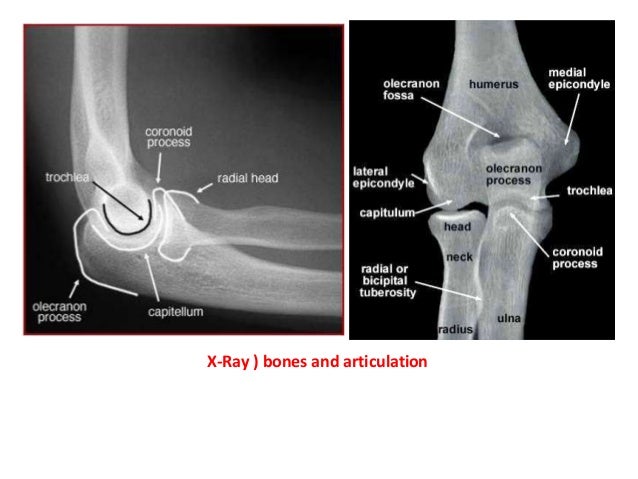

The Elbow Joint In Concern Of Diagnostic Imaging .pptx 1

imaging concern pptx

Bones Of Elbow Joint

elbow bones joint